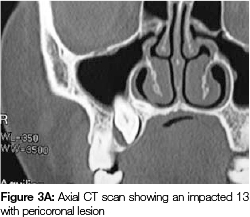

Palatal to this lesion but slightly more distal was an impacted 13 with a small cystic lesion that appeared to be attached to its cervical margin (Figure 3A) and which had caused thinning and slight expansion of the palatal plate. The two lesions were separated by a thin bony margin. (Figure 3B).